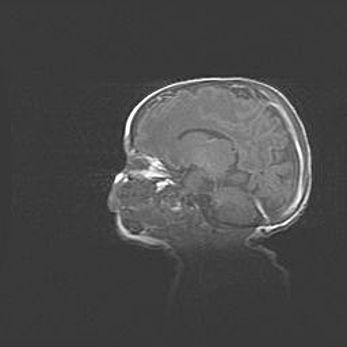

Мальформация Денди-Уокера. Киста задней черепной ямки.

Агенезия мозолистого тела.

Возраст: 2,5 месяца

Вес: 2420 г

Пол: женский

Окружность головы: 37 см

Срок гестации: 32 недели

Мальформация Денди—Уокера — редкий вид патологии ЦНС, представляющий собой врожденный порок развития каудального отдела ствола и червя мозжечка, ведущий к неполному раскрытию срединной (Мажанди) и латеральных (Лушка) апертур IV желудочка мозга. Для этогно синдрома характерна триада симптомов: гипотрофия червя мозжечка и/или полушарий мозжечка, кисты задней черепной ямки, гидроцефалия различной степени. В 70% случаев порок сочетается и с другими аномалиями головного мозга, в частности с агенезией мозолистого тела.